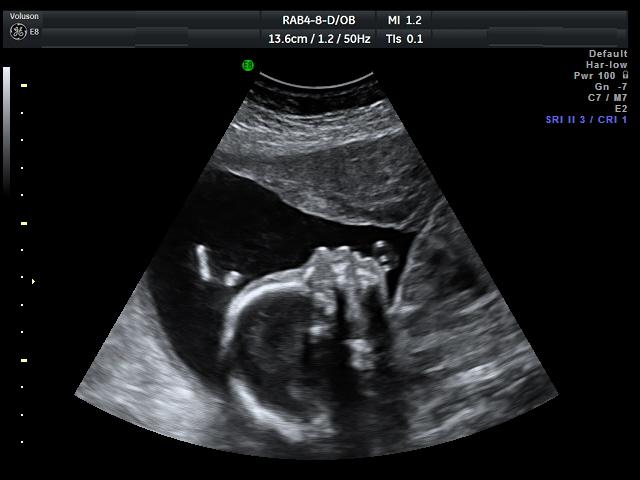

Ahojky byli jsme v nemocnici.........